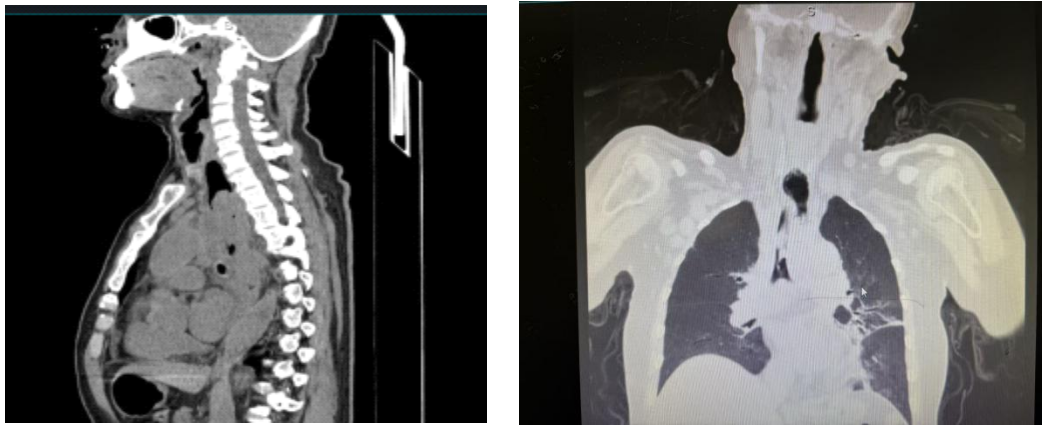

患者入院时情况危急:食管完全梗阻,已十余天无法进食进水;气管下段被肿瘤组织阻塞超过80%,呼吸时刻面临窒息风险;更棘手的是,影像检查提示存在较大的气管食管瘘,随时可能引发致命的吸入性肺炎。

解决营养支持后,团队立即启动气道疏通计划。气管镜下显示气管下段新生物阻塞已达90%,巨大的气管食管瘘口清晰可见。顾兴主任与赵延军副主任协同操作,采用硬镜与软镜双镜联合的方式,在内镜护理团队高效配合下,成功为患者置入气管支架。支架张开后,原本近乎闭塞的气道瞬间变得通畅,同时完美覆盖了瘘口,一举解决了呼吸梗阻和瘘口返流两大难题。